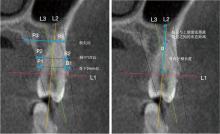

童丽, 顾卫平, 陈岗, 等. 基于CBCT的下颌第一磨牙区即刻种植相关的影像学研究[J]. 口腔医学, 2020, 40(3): 227-231.

刘昕, 丁子凌, 杨晓喻, 等. 锥形束CT测量成人上颌前磨牙根尖与上颌窦位置关系及其对即刻种植的影响[J]. 口腔疾病防治, 2024, 32(6): 444-450.

韦梦瑶, 王晓丽, 李雁, 等. 上颌前磨牙根管变异及其与上颌窦关系的锥形束CT研究[J]. 上海口腔医学, 2018, 27(2): 156-163.

宋颢, 杨梦源, 陆艺文, 等. 上前牙区种植相关解剖因素CBCT研究[J]. 中国临床解剖学杂志, 2023, 41(4): 401-408.